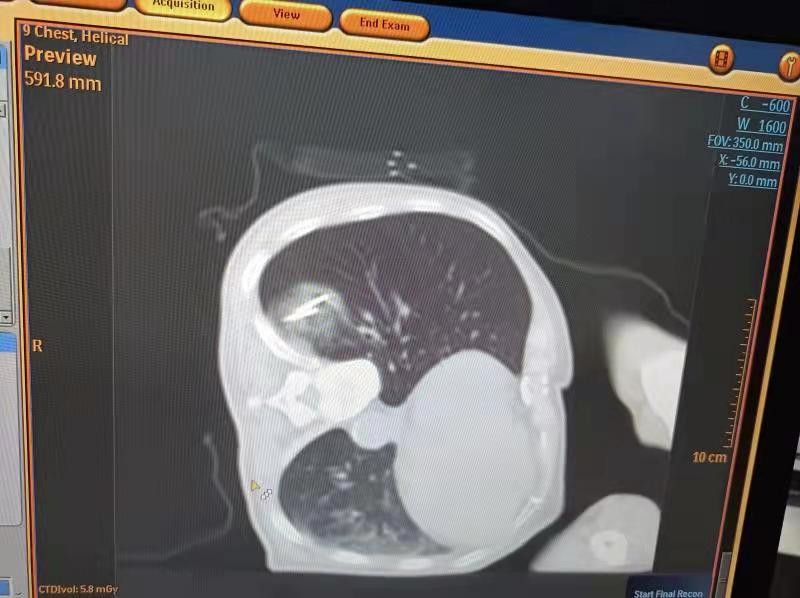

术中经皮局麻下插入氩氦刀冷冻消融针2根,2个循环冷冻后CT可见冷冻范围完全覆盖肺内肿物。术后患者无明显疼痛,观察2天后出院。